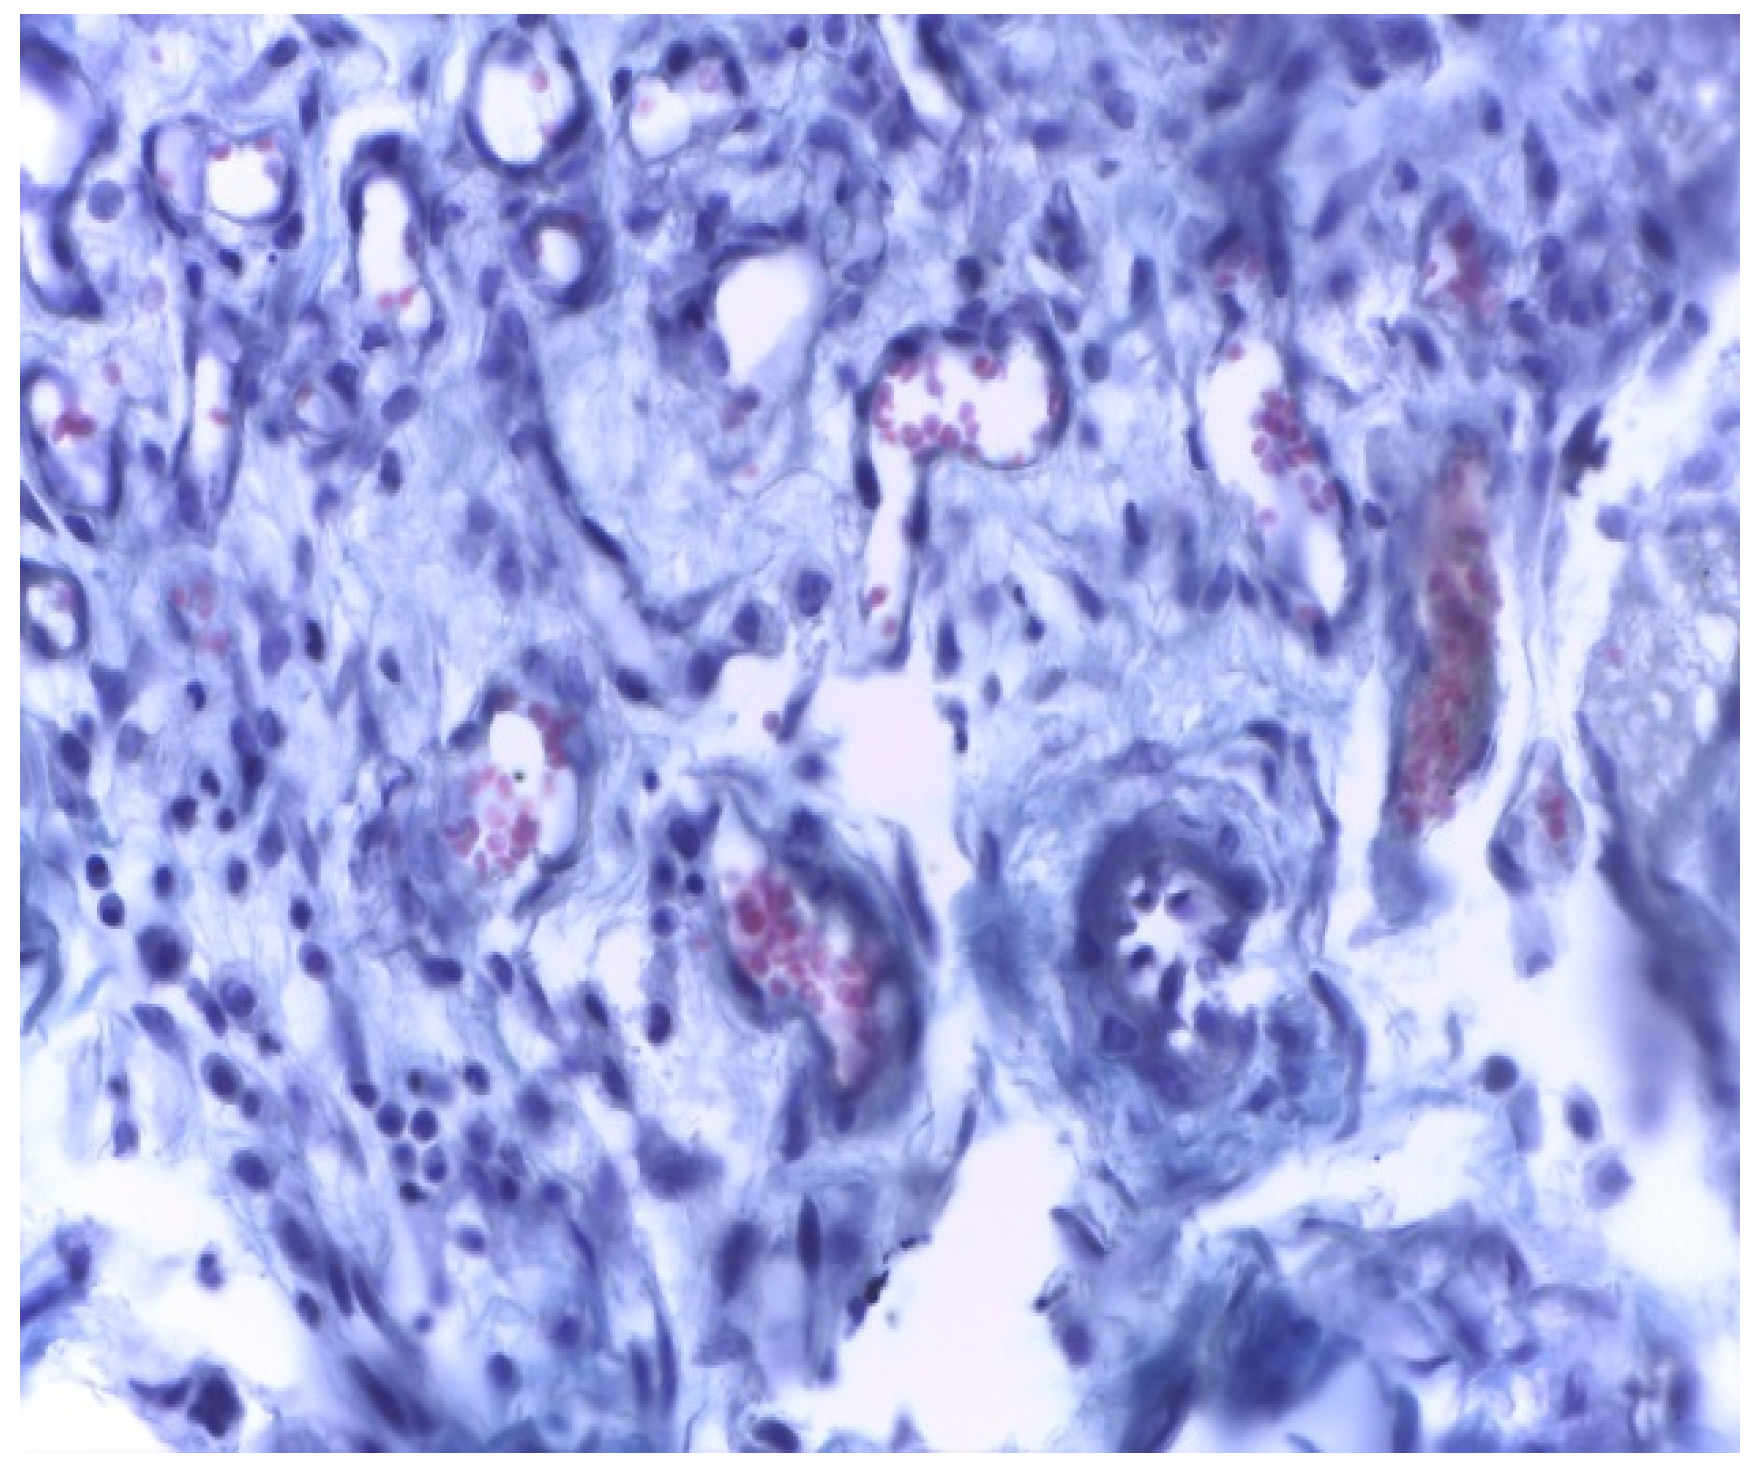

In group A (implanted with MTA) we noticed a well-defined area of peripheral necrosis (surrounding the biomaterial) in which incompletely resorbed MTA fragments and an intense influx of leukocytes consisting of macrophages, histiocytic cells, and neutrophils were present, together with a high number of fibroblasts and collagen fibers (Figure 4 and Figure 5).

Figure 5. Group A. Buffer zone, consisting of fibroblast proliferation and collagen fiber synthesis. Col. Trichrome Masson, ×200.